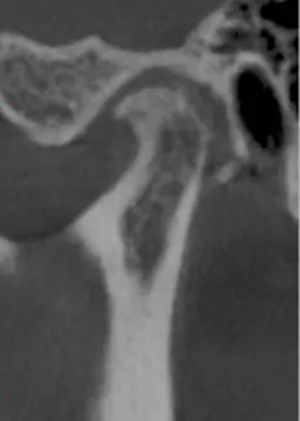

更嚴(yán)重的是會(huì)影響下頜關(guān)節(jié)的健康,正常下頜運(yùn)動(dòng)三模式開(kāi)口運(yùn)動(dòng),側(cè)方咬合,前伸下頜,閉鎖合時(shí)只留開(kāi)口運(yùn)動(dòng)模式了,其他二種只有先開(kāi)口后才能發(fā)生。這樣由于上前牙內(nèi)傾,強(qiáng)迫下頜后退,使下頜關(guān)節(jié)位置異常,關(guān)節(jié)頭越磨越平。這類(lèi)人群往往有關(guān)節(jié)區(qū)疼痛、張閉口彈響,張不開(kāi)口等,嚴(yán)重的會(huì)影響日常生活和情緒。

關(guān)節(jié)頭損傷